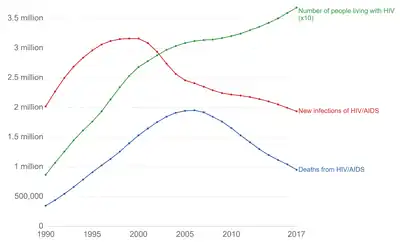

HIV/AIDS is considered a global pandemic.[228] As of 2022, approximately 39.0 million people worldwide are living with HIV, the number of new infections that year being about 1.3 million.[156] This is down from 2.1 million new infections in 2010.[156] Among new infections, 46% are in women and are children globally.[156] There were 630,000 AIDS related deaths in 2022, down from a peak of 2 million in 2005.[156]

Among persons living with HIV (PLWH), the largest proportion reside in eastern and southern Africa (20.6 million, 54.6%). This region also had the highest rate of adult and child deaths due to AIDS in 2020 (310,000, 46.6%). Sub-Saharan African adolescent girls and young women (aged 15-24 years) account for 77% of new infections among this age-range globally [156] Here, in contrast to other regions, adolescent girls and young women are three times more likely to acquire HIV than age-matched males.[156] Despite these statistics, overall, new HIV infections and AIDS-related deaths have substantially decreased in this region since 2010.[229]

Eastern Europe and central Asia has observed a 43% increase in new HIV infections and 32% increase in AIDS-related deaths since 2010, the highest of all global regions.[229] These infections are predominantly distributed in persons who inject drugs, with gay men and other men who have sex with men or persons who engage in transaction sex the second and third populations most impacted in this region.[229]